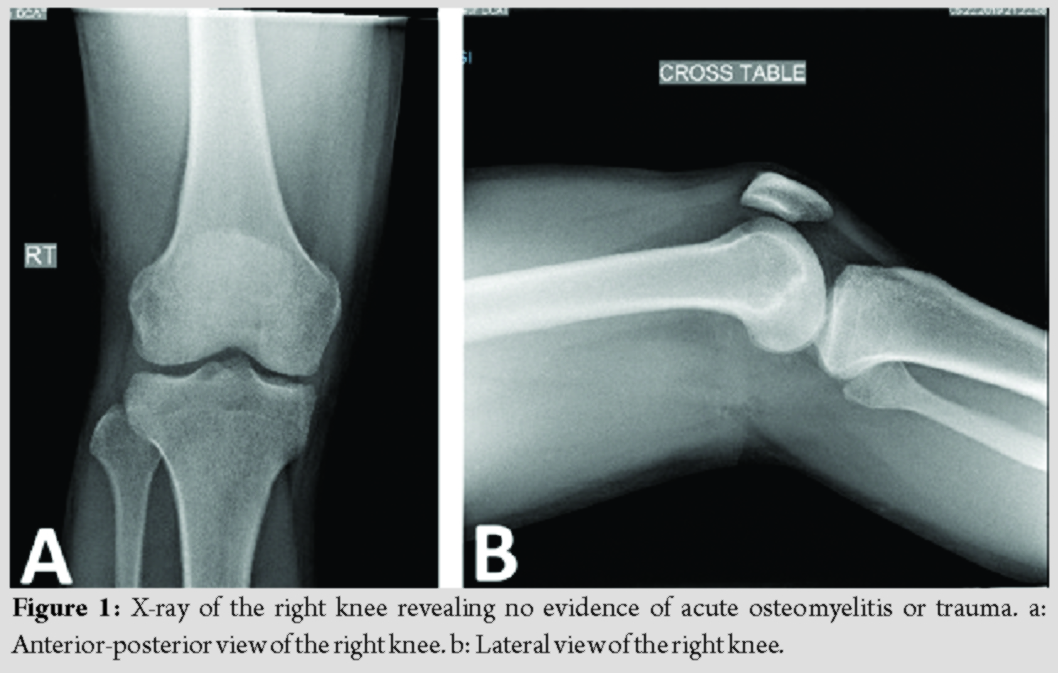

At presentation, the patient stated that this episode did not resolve with rest or anti-inflammatory medication. He reported the drainage had been ongoing for 2 weeks and appeared to come from a punctum in the center of the swelling, but denied any fever, chills, sharp pain, change in sensation, or restriction in active or passive range of motion. X-ray showed no acute OM or fractures (Fig. 1a and b). Magnetic resonance imaging (MRI) of the knee revealed 6.8 × 5.3 × 8.5cm septated fluid collection consistent with a large abscess extending from the subcutaneous adipose tissue along the lateral aspect of the thigh through a perforation in the fascia posterior to the vastus lateralis and tensor fascia lata and anterior to the biceps femoris (Fig. 2a-d). The fluid collection also extended deep between the muscle bellies to the level of the posterior lateral cortex of the distal femoral diaphysis. Diffuse soft-tissue edema was visualized; however, no periosteal or marrow edema was present, confirming the absence of acute OM (Fig. 3a and b).